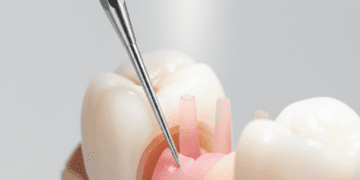

Quando a recessão alcança níveis significativos, procedimentos cirúrgicos podem ser necessários para restaurar a margem gengival. Entre as técnicas mais comuns, destacam-se:

- Enxerto gengival livre: Consiste na retirada de tecido gengival da região do palato para cobertura da raiz exposta.

- Enxerto de tecido conjuntivo: Técnica que utiliza uma camada do tecido abaixo da gengiva do palato para recobrir a área afetada, favorecendo a cicatrização e a formação de nova gengiva.

- Retalho gengival: Levantamento da gengiva local para reposicionamento e melhor cobertura da raiz.